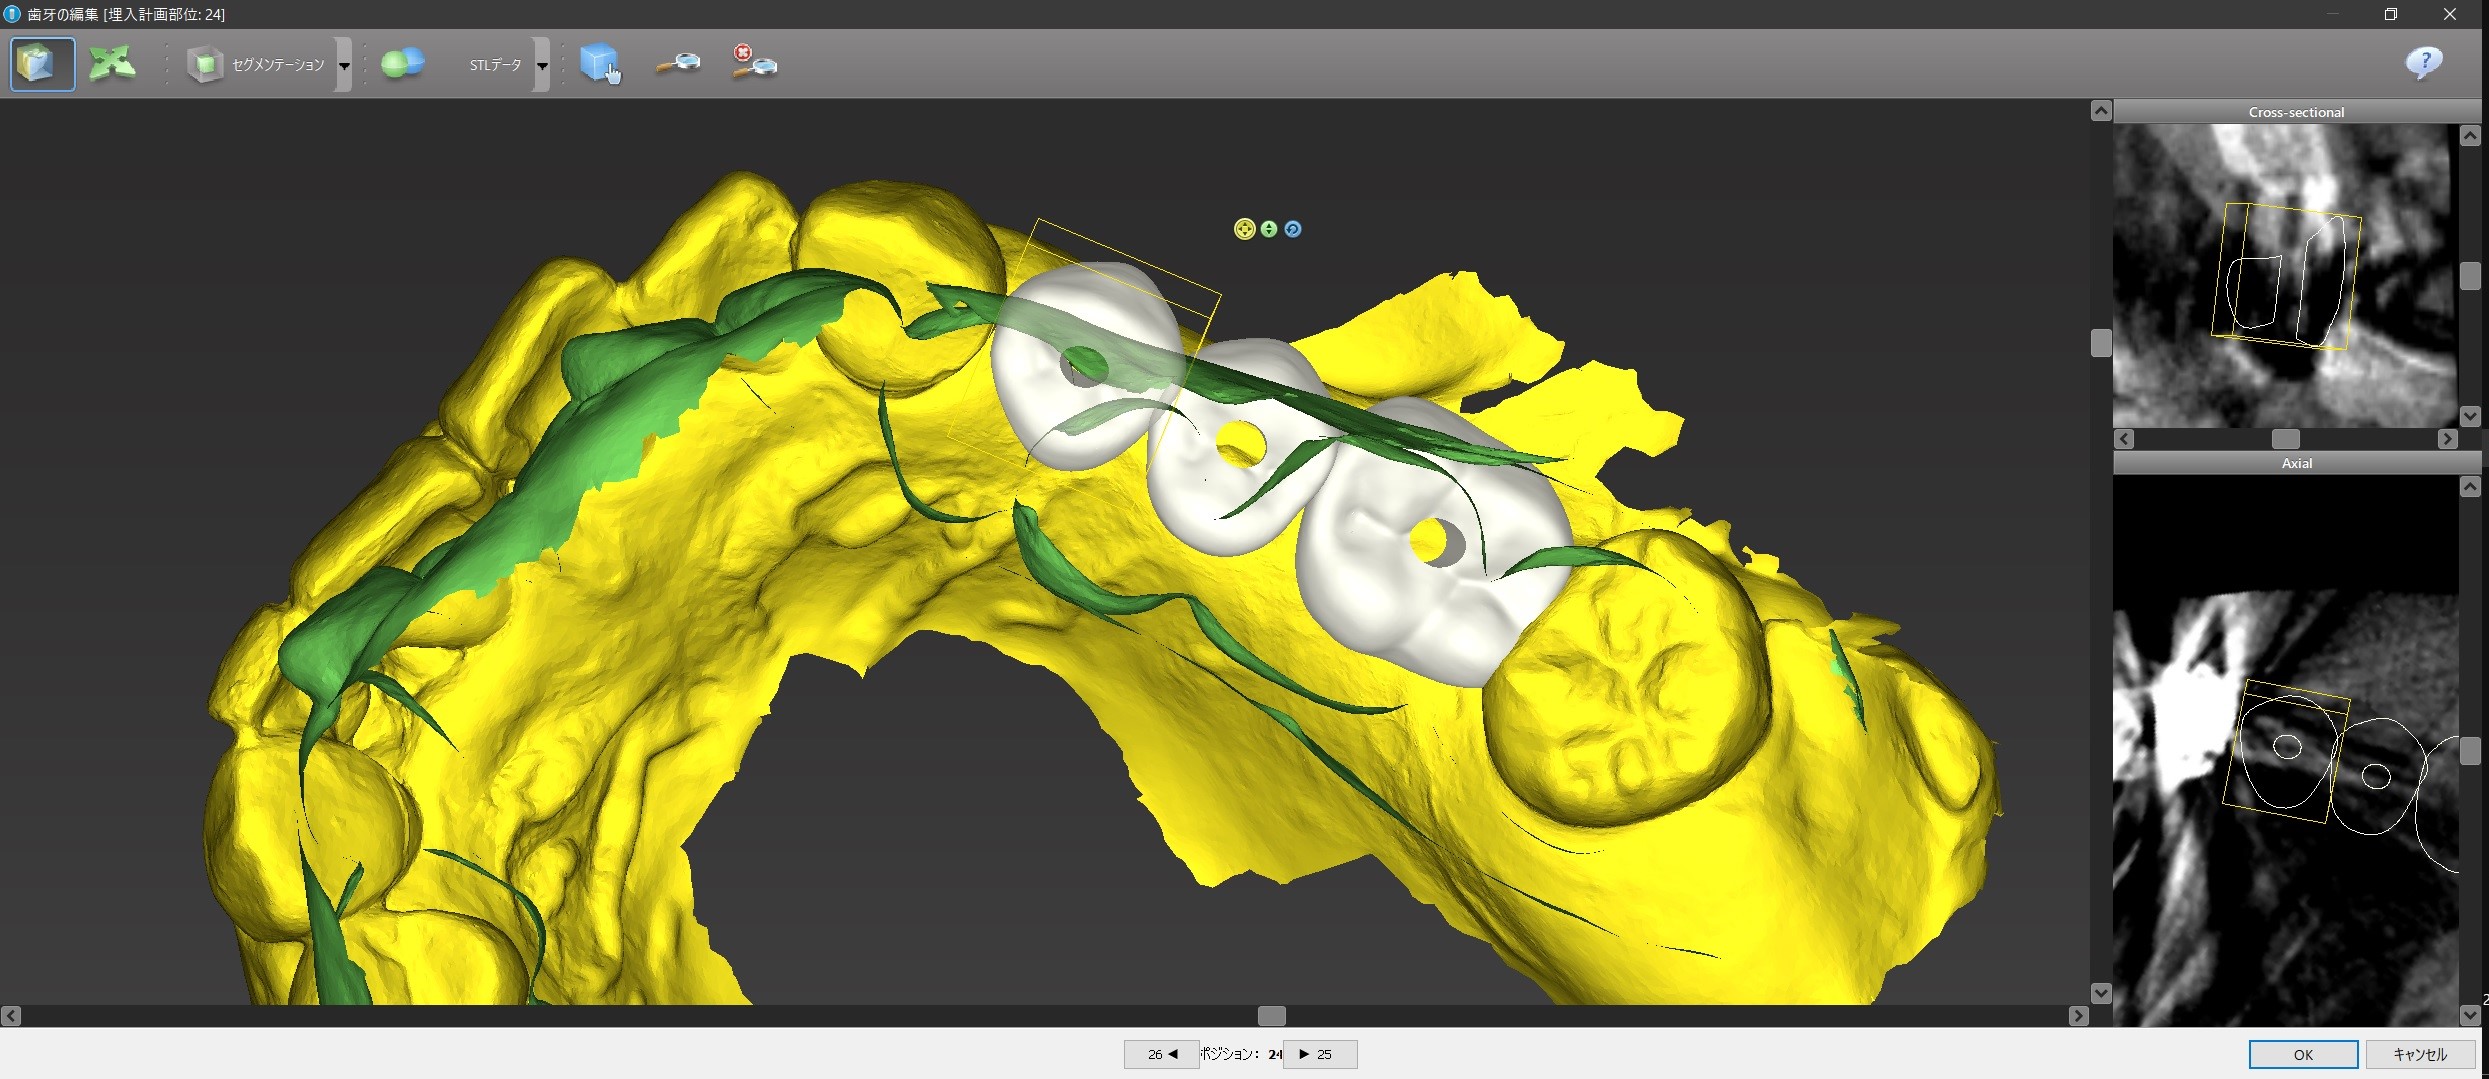

コンピュータ画面上で、下から見たり、裏から見たり、どアップで見て細かい調整をすることができます。

インプラントの位置のシュミレーション

このように、まず先に上部構造の位置をシュミレーションするのです。

今回で言えば、インプラントを前から順に#24、#25、#26と呼ぶと

① #24がその前の天然歯に当たって、そもそもこの位置に入れられない。

② 前述のように#24上部構造が下の歯と咬まない。ちゃんと咬むようにするためには矯正治療が必要になる。

③ #24のインプラントと上部構造との間に角度を付けるか、もしくはGBR(骨を増やす、作る処置)が必要になる。

④ #25インプラント部位に歯の根が残っているので、これをインプラント手術の時に取り除くのと同時にそこに骨を増やす処置が必要になる。

今回、④の問題は対応が優しく、#25、#26部位はインプラントを入れる条件がかなり良いため、#24にはインプラントを入れずに#25と#26にだけインプラントを入れて、それを土台としたインプラントブリッジの設計にして、#24が下と咬まないことはご了承して頂くか矯正治療をするか相談するということになります。